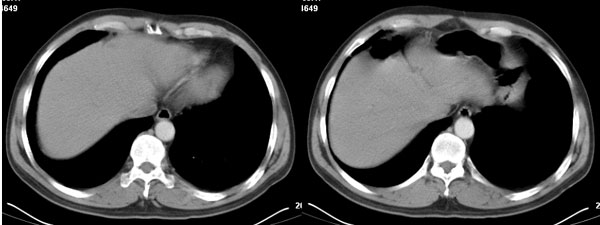

李**,男,46岁,便血1天入院,慢性贫血貌,腹平、软,剑突下压痛,肠鸣音稍活跃,hb大于1g/l,胃镜:慢性浅表性胃炎,b超:1肝内多发性占位 2腹腔内囊性肿块 ,肝内圆形影平扫ct值42.9,动脉期48.6,静脉期58.2,延迟期62.2

影像学表现:1 腹腔前中部、胰腺前方囊实性病灶(个人认为确定有否实性成分存在这是关键,涉及到鉴别诊断,如果是口服阳性造影剂则可明确左侧是不是小肠了),囊性部分囊壁不均,实性部分有强化,与小肠关系较密切,局部小肠受推移;与胰头、胃后壁均有脂肪间隙存在;2 胰腺无异常改变,胰周无渗出;3肝后段包膜下2个小圆形低密度灶,从图像和楼主提供的ct值来看有轻度强化,灶周无片状强化,不似单纯囊肿及肝癌、炎性病变表现;4 腹膜后及腹腔内无淋巴结肿大。

胰腺边界清晰,胰周筋膜不厚,胰周脂肪密度无明显增高;其前方囊实性病灶,边界清晰,增强后实性部分轻度强化;肝内多发边界清晰低密度影,增强后无明显强化(平扫ct值42.9,动脉期48.6,静脉期58.2,延迟期62.2)。